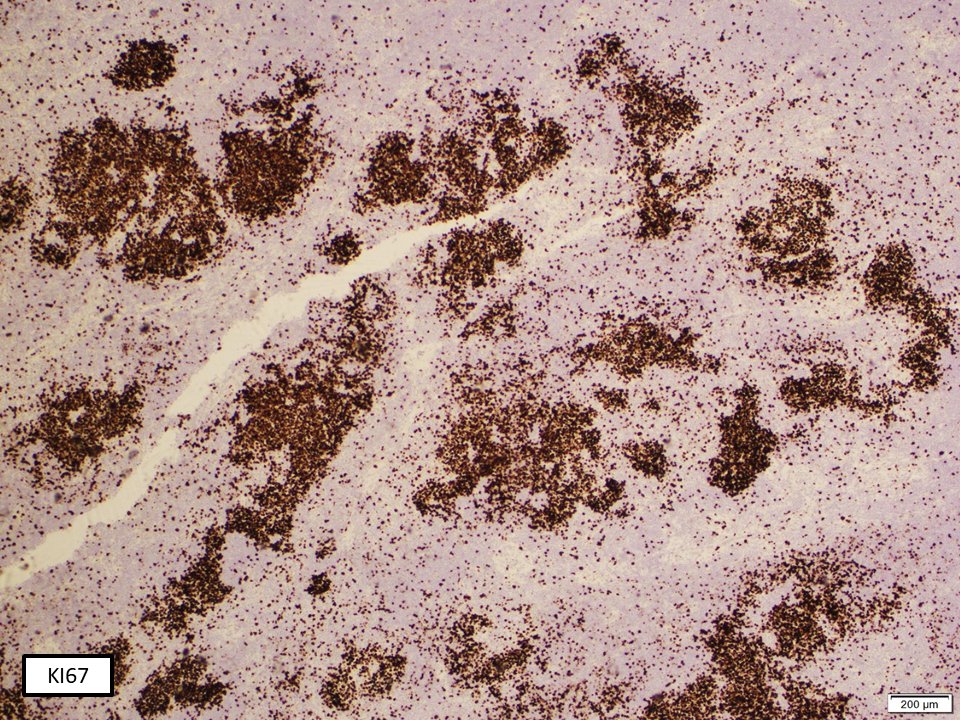

(2/3) CD21 stain highlights expanded and disrupted follicles by large cell lymphoma. Ki67 is remarkably high in the large cell transformation area, in comparison to background low grade FL #hemepath #LJMFridayUnknowns #VirtualHemepathMDA #lymsm #endcancer